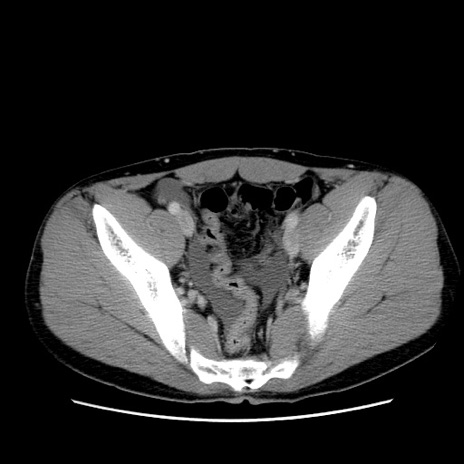

症例36(横断像)

【症例】20歳代 男性

【主訴】心窩部痛

【現病歴】今朝より上腹部痛あり。一旦軽快していたが再度出現したため救急要請。昨日夕に白身の魚を含む刺身を食べた。

【身体所見】BP 136/89mmHg、HR 74/min、BT 37.0℃、腹部:膨満、軟、心窩部に圧痛あり。反跳痛なし、筋性防御なし、腸雑音やや亢進あり。

【データ】WBC 17700、CRP 0.48